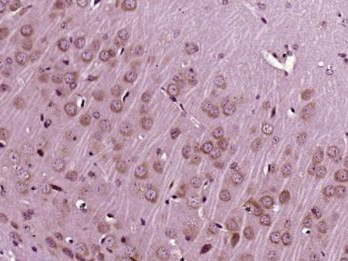

| 产品图片 | ![]() Paraformaldehyde-fixed, paraffin embedded (Mouse brain); Antigen retrieval by boiling in sodium citrate buffer (pH6.0) for 15min; Block endogenous peroxidase by 3% hydrogen peroxide for 20 minutes; Blocking buffer (normal goat serum) at 37°C for 30min; Antibody incubation with (IGF 1) Polyclonal Antibody, Unconjugated (bs-0014R) at 1:400 overnight at 4°C, followed by operating according to SP Kit(Rabbit) (sp-0023) instructionsand DAB staining. ![]() Paraformaldehyde-fixed, paraffin embedded (Rat brain); Antigen retrieval by boiling in sodium citrate buffer (pH6.0) for 15min; Block endogenous peroxidase by 3% hydrogen peroxide for 20 minutes; Blocking buffer (normal goat serum) at 37°C for 30min; Antibody incubation with (IGF 1) Polyclonal Antibody, Unconjugated (bs-0014R) at 1:400 overnight at 4°C, followed by operating according to SP Kit(Rabbit) (sp-0023) instructionsand DAB staining. |